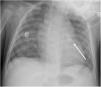

An early post-procedure complication rate of 1.8% was found (four patients). Three patients presented isolated loss of arterial pulse and were successfully treated with fibrinolytics. The most severe complication was in a seven month-old patient who presented device embolization 48 hours after the procedure. In this infant with a history of prematurity (born at 26 weeks of gestation), an Amplatzer duct occluder II Additional Sizes (5x6 mm) had been implanted. Loss of lower limb arterial pulse was noted a few hours after the procedure. A vascular doppler ultrasound confirmed occlusion of the femoral artery and thrombolysis with recombinant tissue plasminogen activator was started. After 48 hours, a chest radiograph revealed the device had migrated (Figure 13), with computed tomography confirming the device was at an inferior lobar branch of the left pulmonary artery. This required urgent surgical removal of the Amplatzer duct occluder II Additional Sizes and PDA ligation, which were both uneventful.